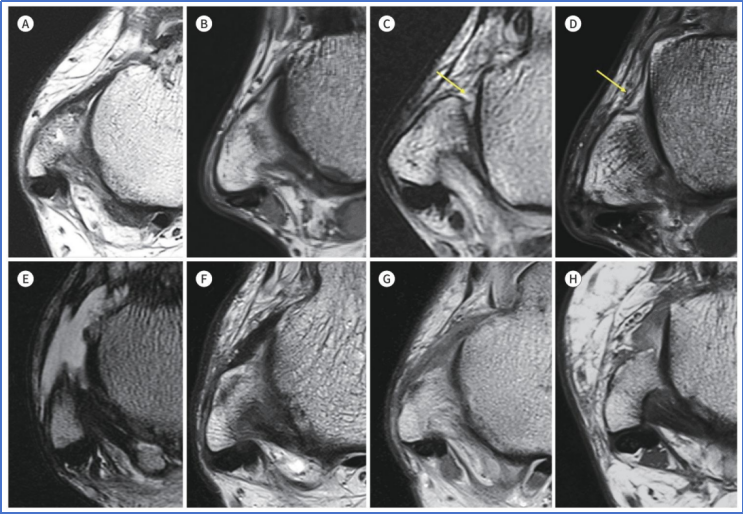

图 6. 慢性外侧踝关节不稳(CLAI)患者在轴位 T2 加权像或质子密度加权像上,前距腓韧带(ATFL)的形态多样性:(图 A)正常前距腓韧带(ATFL);(图 B)变薄的前距腓韧带(图 C)变薄前距腓韧带的连续性中断(箭头所示);(图 D)变薄且呈波浪状的前距腓韧带(箭头所示);(图 E)前距腓韧带缺如;(图 F)增厚的前距腓韧带;(图 G)信号强度增高的增厚前距腓韧带;(图 H)信号强度增高且呈波浪状的增厚前距腓韧带。